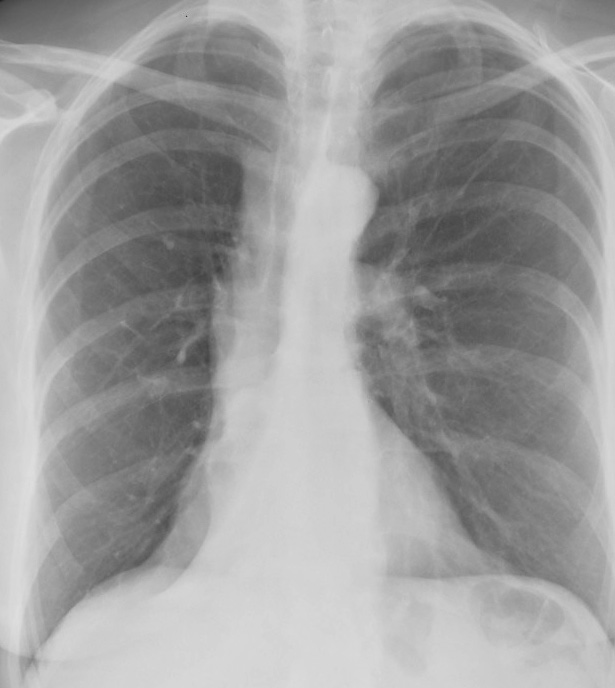

RLL Collapse 1 PA